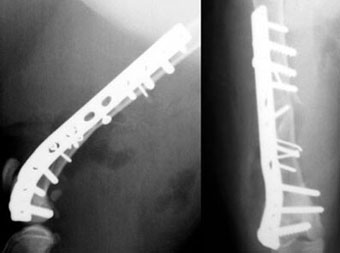

体重6kgの猫の大腿骨粉砕骨折。

膝関節近くまでひび割れており、難易度の高い症例でした。

中央部骨片をラグスクリューと細ピンでひとつにまとめた後、膝関節部に合わせてベンディングしたプレートを用いて固定しました。

写真上段: 手術前

写真下段: 手術後

膝関節ぎりぎりまでスクリューをいれてます。